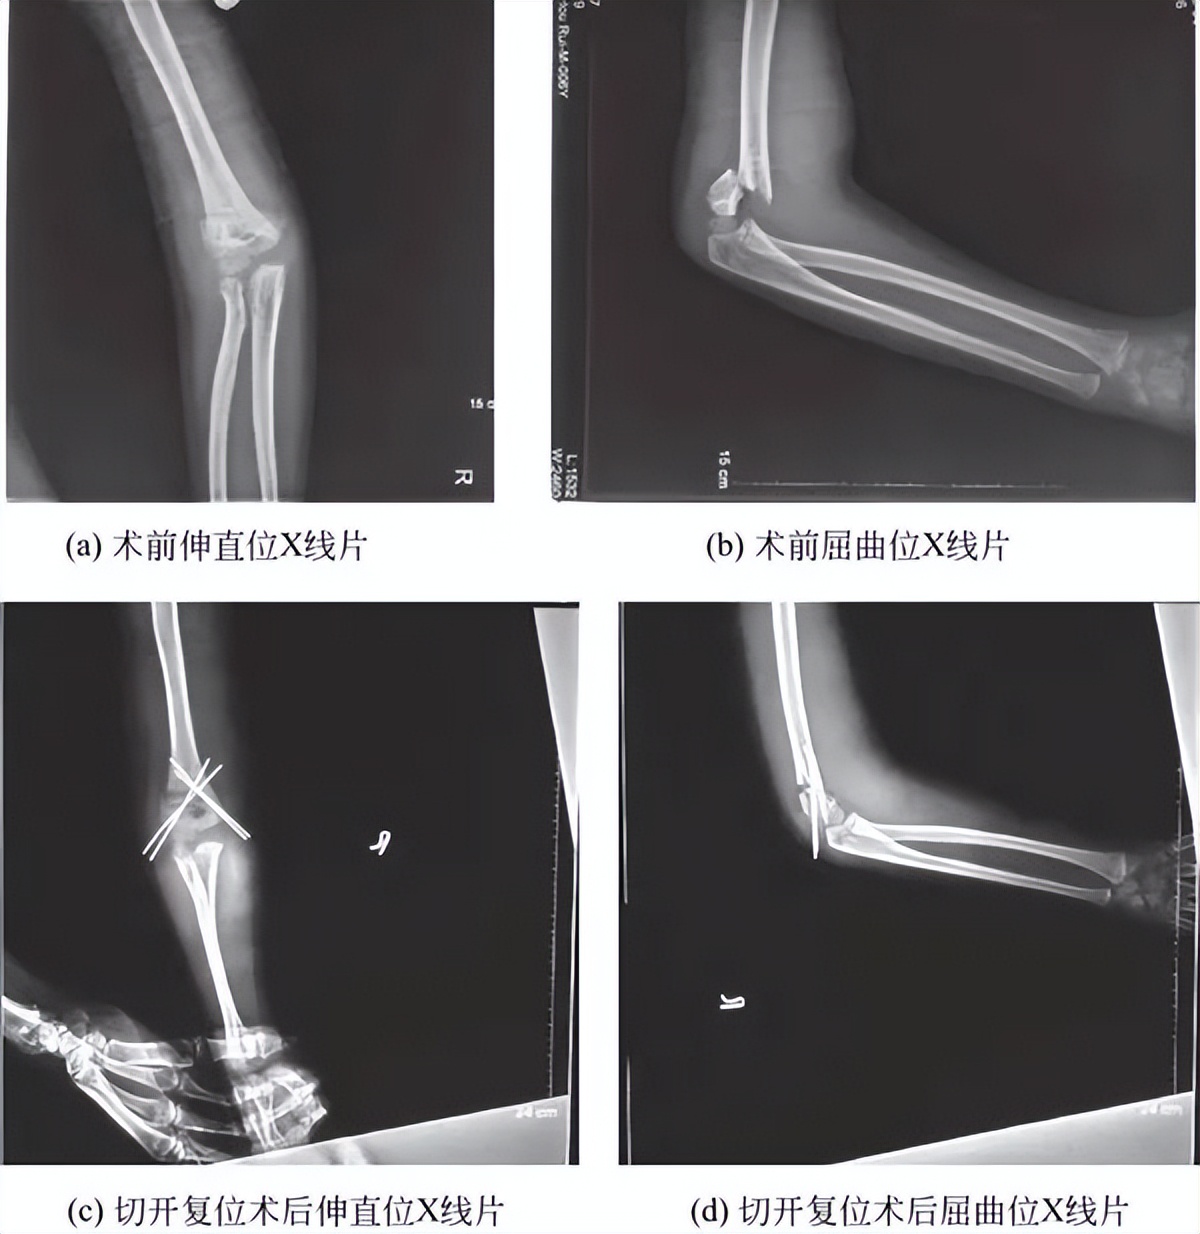

(3)Ⅲ型肱骨髁上骨折:所有的Ⅲ型肱骨髁上骨折复位经皮克氏针内固定是目前Ⅲ型髁上骨折的标准治疗方法。通常可闭合复位经皮克氏针内固定,但若软组织嵌入不能解剖复位或存在肱动脉损伤者需切开复位(图2)。

图2 肱骨髁上骨折术前术后X线片

肱骨髁上骨折切开复位手术入路有4种:①肘外侧入路(包括前外侧);②肘内侧入路;③肘内侧、外侧联合入路;④肘后侧入路。